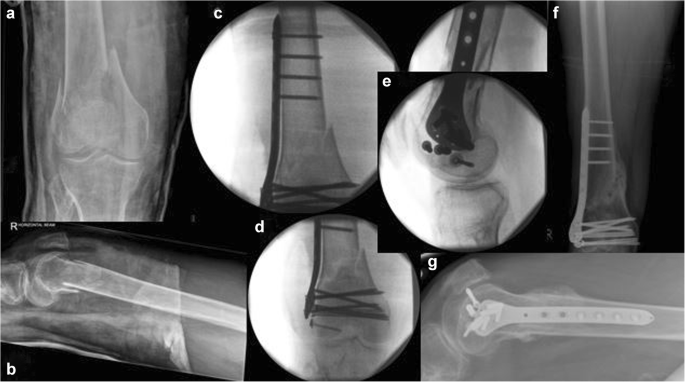

Fig. 5

figure 5

Type 33.A2 distal femoral fracture of a 92-year-old lady following a fall at her garden (a and b represent pre-operative anteroposterior and lateral views of the right distal femur). Of note, an ipsilateral cemented Thompson’s hemiarthroplasty. Randomised and treated with a LISS plating system inserted with a mini invasive technique, spanning proximally the stem of the hemiarthroplasty to neutralise an in-between implants stress riser (d, e, f). The fracture was noted to be fixed and was malunited in 15° of the valgus (c and d). The same patient underwent further surgery 9 months later whereas two of the metaphyseal locking screws were removed as they were found to be irritating the soft tissues over the medial femoral condyle (c)